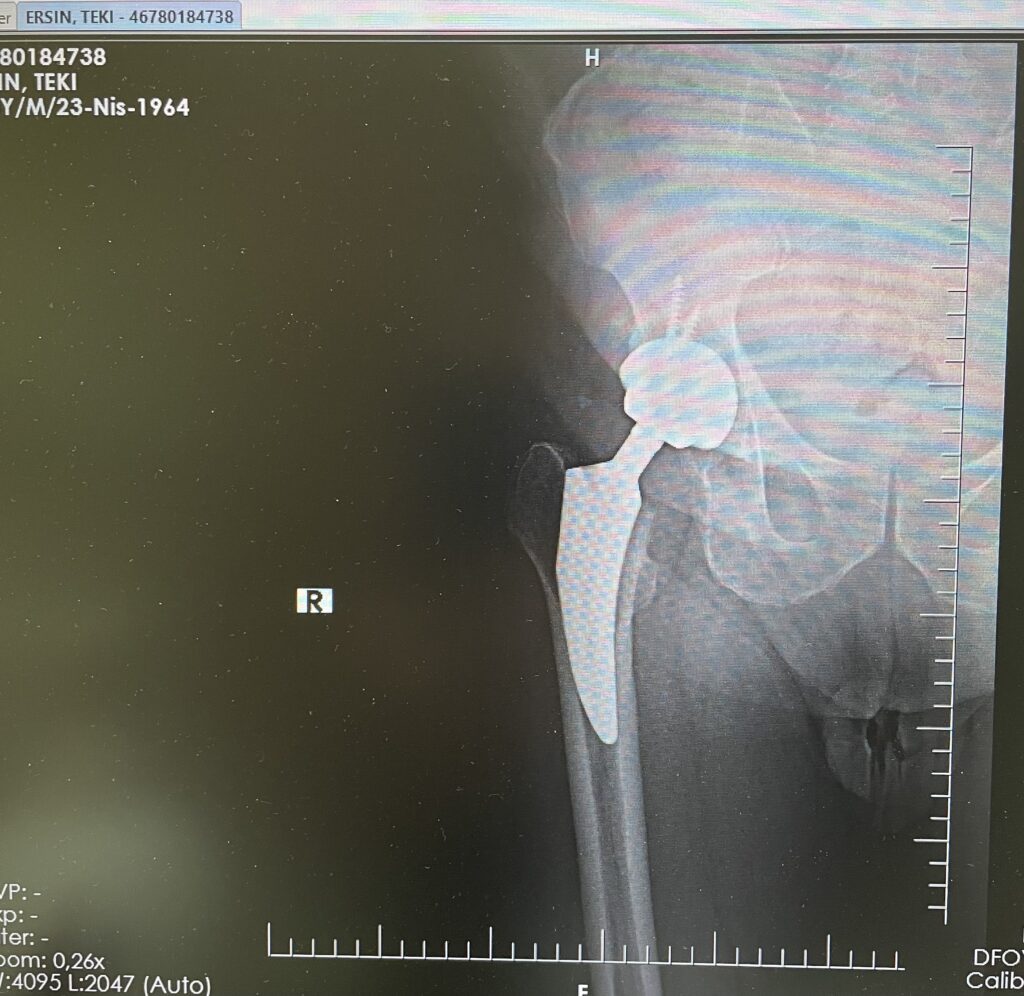

E.T.